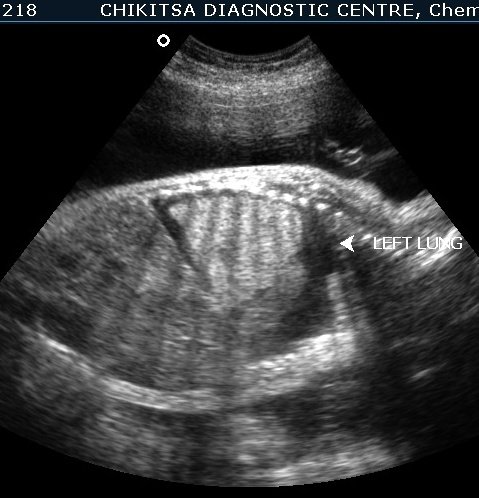

Ultrasound FInding

The left lung was hyperechoic and enlarged. The heart was displaced to the right, compressed, and consequently small. The right lung was compressed and hypoplastic. Hydrops was present, secondary to cardiac failure, manifested by bilateral pleural effusions, mild ascites, and generalized subcutaneous edema.

Compression of the heart and the great veins draining into the right atrium (SVC and IVC) likely contributed to the reduced cardiac size, decreased venous return, and diminished stroke volume, ultimately resulting in cardiac failure and hydrops.